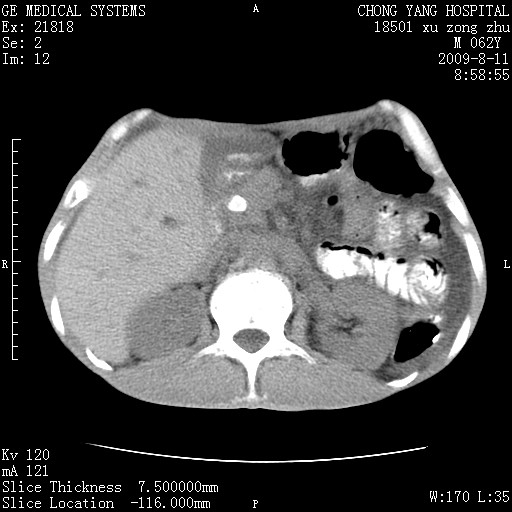

以下是引用杀毒软件在2009-8-11 16:35:00的发言:[br]肝内胆管扩张局限于左叶,胆管内有结石伴肝外胆管结石,胆管壁增厚呈弥漫性并发腹腔积液,胰腺边界模糊。[br][br]考虑---胆总管及肝内胆管结石继发胆管炎及胰腺炎,左肾下极囊肿,腹水。

以下是引用zjzjr在2009-8-11 17:35:00的发言:[br]肝内胆管扩张局限于左叶,胆管内有结石伴肝外胆管结石,胆管壁增厚呈弥漫性并发腹腔积液。[br][br]考虑---胆总管及肝内胆管结石继发胆管炎,左肾下极囊肿,腹水。